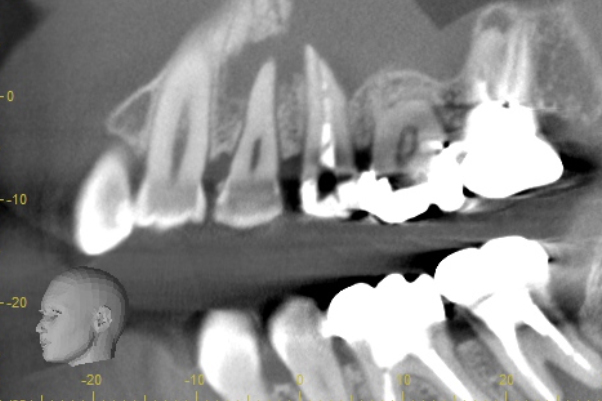

こちらは虫歯で神経を取らないといけなくなりましたが、何度治療しても痛みが消えないと言うことで当院にいらっしゃいました。度重なる治療で歯の神経のあった場所がかなりひろげられており、また根の先端も破壊されている状態でした。ですので、痛みが消えないのです。

肉眼では根の先端は見ることができませんがマイクロスコープでは見ることができます。根の先端をこれ以上破壊しないように清掃して歯の神経があった場所にお薬を詰めることができました。根の治療後、かぶせ物までして半年たっても痛みがありません。

レントゲンを見ていただいて、歯の先までしっかり白いお薬が入っているのがわかります。